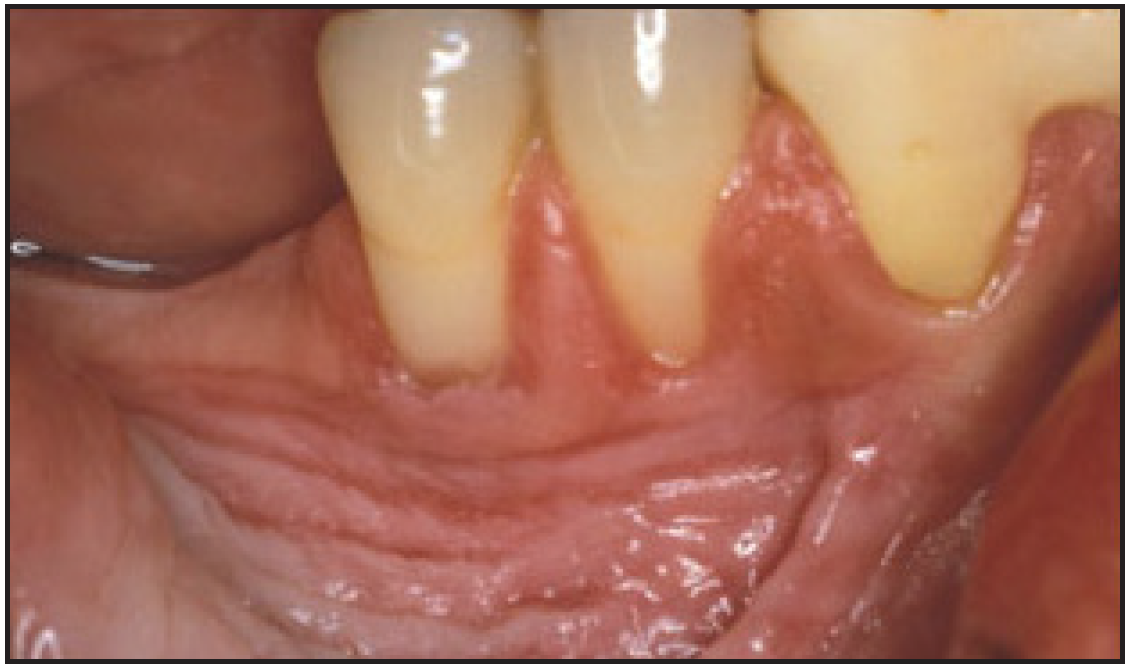

Smokeless tobacco use can result in halitosis, staining, abrasion of the teeth, gum recession, and dental caries.27 Smokeless tobacco manufacturers add other compounds to their products to achieve the flavors their customers want, such as cane sugar, honey, licorice, or rum and abrasives. These components of smokeless tobacco, along with poor oral hygiene can cause extensive gingival attachment loss and carious lesions on the exposed root surface. Focal gingival recession with periodontal attachment loss and bone erosion occurs frequently on the facial surfaces of the teeth where the tobacco is held. This recession is a result of the irritation caused by the toxic chemicals and abrasives found in smokeless tobacco. It is not uncommon to find substantial amounts of root surfaces exposed at the tobacco placement site. With the root surface exposed, there is an increased risk of hot and cold sensitivity.28 Bleeding is less common because of the vasoconstriction properties of nicotine.27

Figure 9 – Gingival Attachment Loss. Image provided by: Dr. JE Bouquot

Figure 9